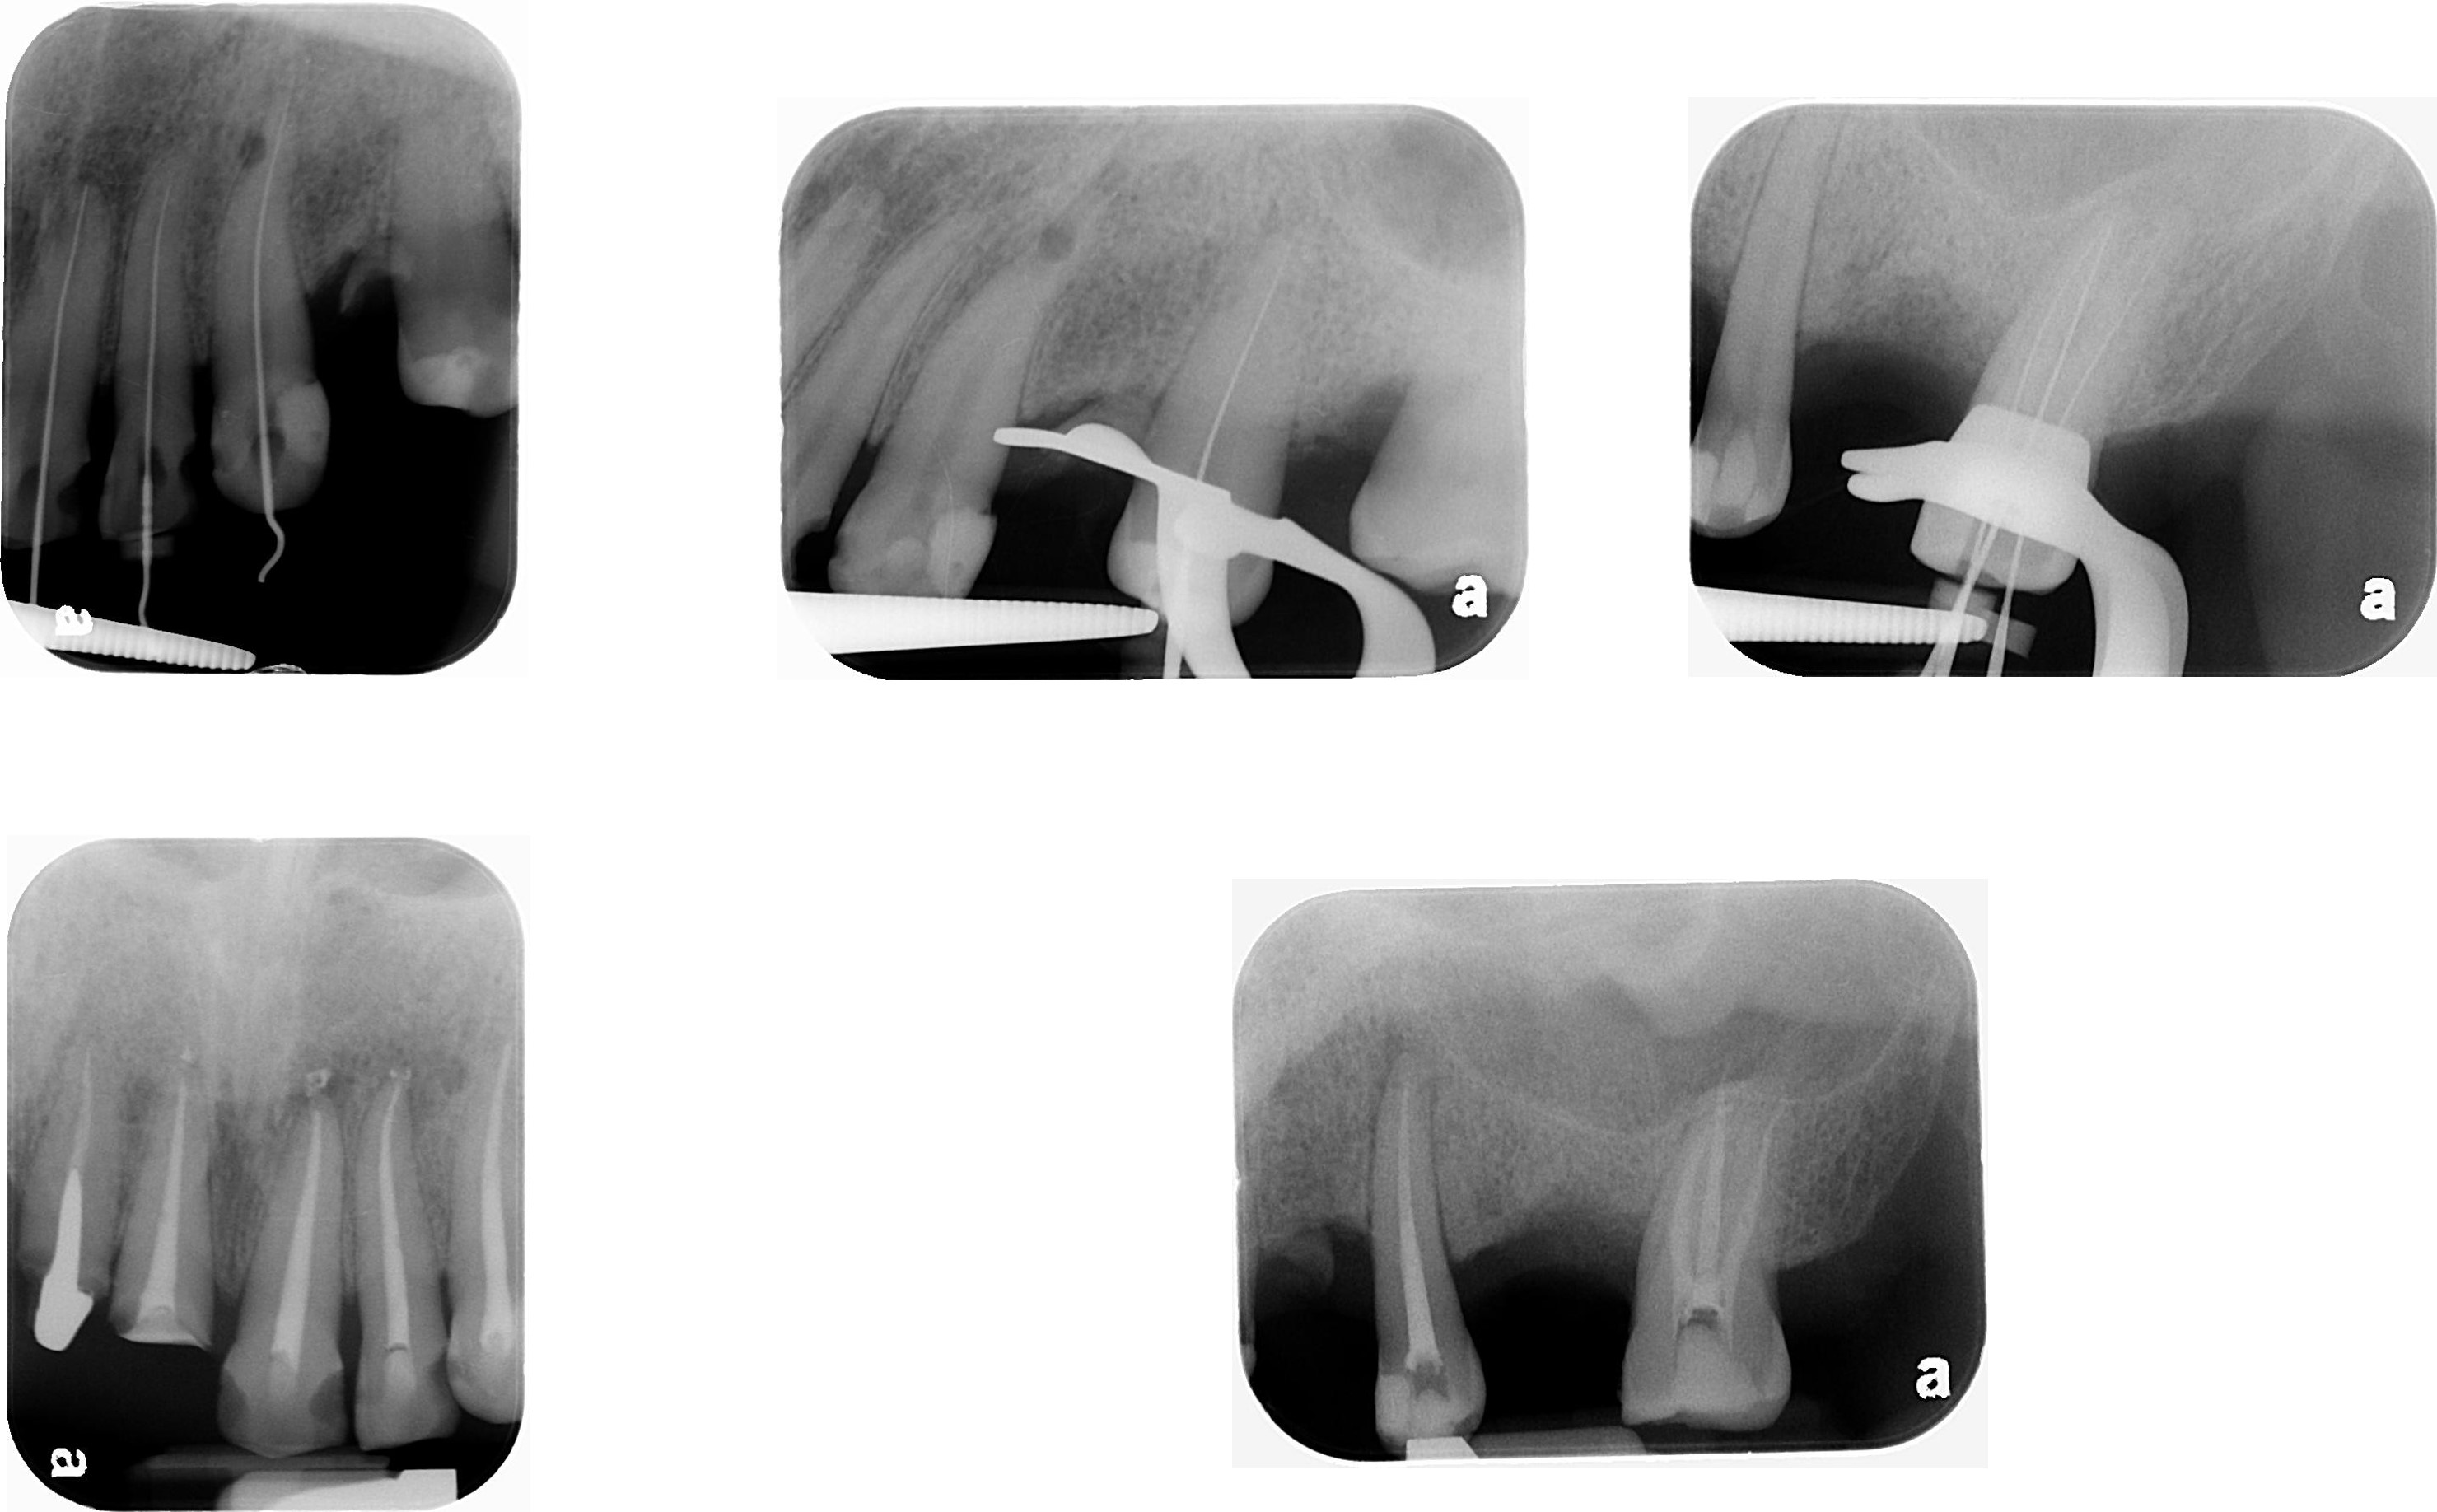

上顎牙齒根管治療

移除舊釘柱

膺復前評估